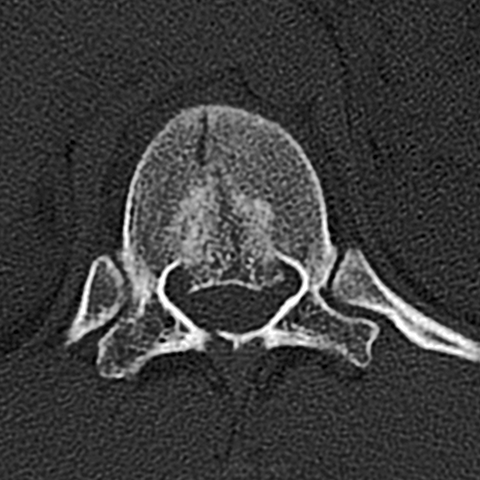

40 year-old man who fell from a tall ladder complains of back pain [2 of 2]